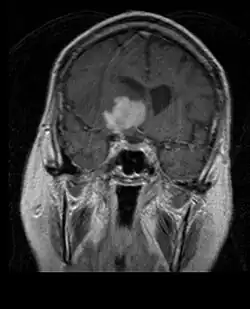

Na -MRI ukazuje intrakraniální tumor jako masivní lézi, která se po použití kontrastní látky může stát více luminiscenční. Vždy však dojde k anomálii signálu -Magnetická rezonance, která indikuje přítomnost neoplazie nebo vazogenního edému. Obvykle zvýšená luminiscence (zesílení kontrastu) svědčí pro nádor vyššího stupně malignity. Pro glioblastom je charakteristický kontrastní prstenec, jehož luminiscenční část odpovídá vitální části maligního nádoru a tmavší -hypointense oblast odpovídající nekróze tkáně.

Pacienti trpí řadou charakteristických symptomů fokální nebo multifokální masivní léze. MRI obvykle ukazuje nádory s homogenním zvýšením kontrastu v hluboké periventrikulární bílé hmotě. Pro pacienty s oslabeným imunitním systémem je typická multifokalita a nehomogenní zesílení. Analýza lymfomu CNS je mimořádně důležitá v diferenciální diagnostice neoplazie mozku. Je třeba poznamenat, že podávání kortikosteroidů může vést k úplnému vymizení zesílení, což ztěžuje diagnostiku lézí. V důsledku toho, má-li být lymfom CNS zvažován v diferenciální diagnóze, je třeba se kortikosteroidům vyhnout, pokud hromadný účinek nezpůsobí u pacienta závažný a bezprostřední problém.